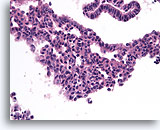

Papilloom, Borst FNA, Celblok.

Met een sterkere vergroting kan een gemengde celpopulatie gezien worden die het oppervlak en de onderliggende melkgangen bekleden. Een rij myoepitheliale cellen is zichtbaar tussen de ductale cellen en het onderliggende stroma (pijl). Let op de spleetachtige ruimte die kenmerkend is voor typische hyperplasie (open pijl).

40X

Papilloom, Borst FNA, Celblok.

Met een sterkere vergroting kan een gemengde celpopulatie gezien worden die het oppervlak en de onderliggende melkgangen bekleden. Een rij myoepitheliale cellen is zichtbaar tussen de ductale cellen en het onderliggende stroma (pijl). Let op de spleetachtige ruimte die kenmerkend is voor typische hyperplasie (open pijl).

40X

Papilloom, Borst FNA, Celblok.

Let op de bijmenging van bleke myoepitheliale cellen (pijlen) en de rijping van de ductale cellen wanneer zij zich verder van het basaalmembraan stratificeren (open pijl).

40X

Papilloom, Borst FNA, Celblok.

Let op de bijmenging van bleke myoepitheliale cellen (pijlen) en de rijping van de ductale cellen wanneer zij zich verder van het basaalmembraan stratificeren (open pijl).

40X